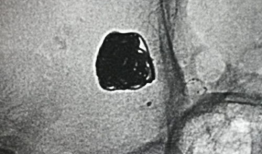

你知道吗?最近我在网上看到一个超级有趣的造影视频全过程,简直就像是一部迷你电影,让我忍不住想要和你分享一下。这个视频详细记录了整...